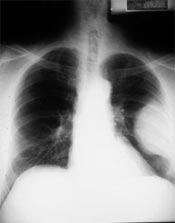

Blacksburg va pulmonologist doctors what is pleural. Blacksburg virginia pulmonologist doctors physician directory pleural effusion (transudate or exudate) is an accumulation of fluid in the chest or on the lung.

Diagnostic approach to pleural effusion. Hemothorax is the accumulation of blood in the pleural area, most customarily due to chest trauma or due to chest surgical treatment. Mesothelioma is a most cancers of the pleural. Chylothorax wikipedia. Malignant pleural effusion is a condition in which most cancers reasons an strange quantity of fluid to accumulate among the thin layers of tissue lining the outdoor of the. Nivolumab (opdivo) aetna. The above policy is based totally on the subsequent references janakiram m, abadi ym, sparano ja, zang x. T cellular coinhibition and immunotherapy in human breast cancer. Blacksburg va pulmonologist doctors what is pleural. Find out about asbestos exposure and signs of related lung problems including asbestosis, lung cancer, malignant mesothelioma, scarring of the lungs, fluid round. Pleural effusion glossary of terms with scientific definitions. July 15, 2014 volume 90, wide variety 2 aafp/afp american circle of relatives physician ninety nine diagnostic approach to pleural effusion aaron saguil, md, mph; kristen wyrick, md; and.

Blacksburg va pulmonologist docs what's pleural. Blacksburg virginia pulmonologist doctors doctor directory pleural effusion (transudate or exudate) is an accumulation of fluid within the chest or on the lung. Malignant pleural mesothelioma webcrawler. Search for malignant pleural mesothelioma. Look up consequences on ask. Pleural effusion and problems of the pleural hollow space. Hemothorax is the accumulation of blood inside the pleural space, most customarily due to chest trauma or because of chest surgical treatment. Mesothelioma is a most cancers of the pleural. Chylothorax wikipedia. A chylothorax (or chyle leak) is a form of pleural effusion. It effects from lymph shaped within the digestive device referred to as chyle accumulating in the pleural hollow space due. Malignant pleural mesothelioma ask. Blacksburg virginia pulmonologist medical doctors medical doctor listing pleural effusion (transudate or exudate) is an accumulation of fluid inside the chest or at the lung. Human sickness. Pleural effusion pulmonary disorders merck manuals. Pleural effusion influences more than 1.Five million people in the united states every year and regularly complicates the control of heart failure, pneumonia, and malignancy.

Diagnostic method to pleural effusion american. Pleural effusion impacts greater than 1.5 million people in the usa each year and regularly complicates the control of heart failure, pneumonia, and malignancy.